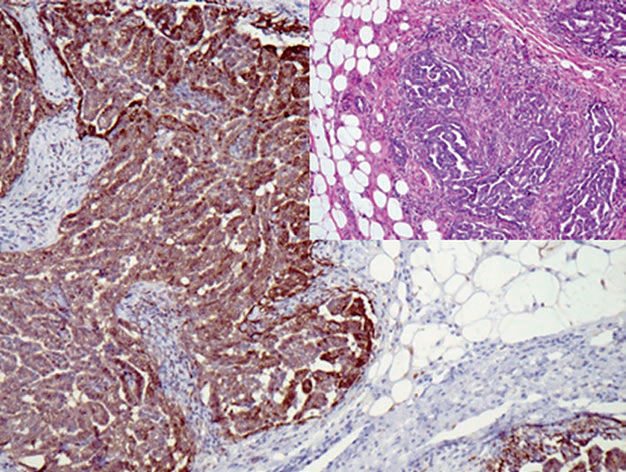

图1. 免疫组化calretinin,清晰的显示出浸润至胸壁的间皮瘤。

图3. 免疫组化D2-40,清晰的显示出浸润至胸壁的间皮瘤。